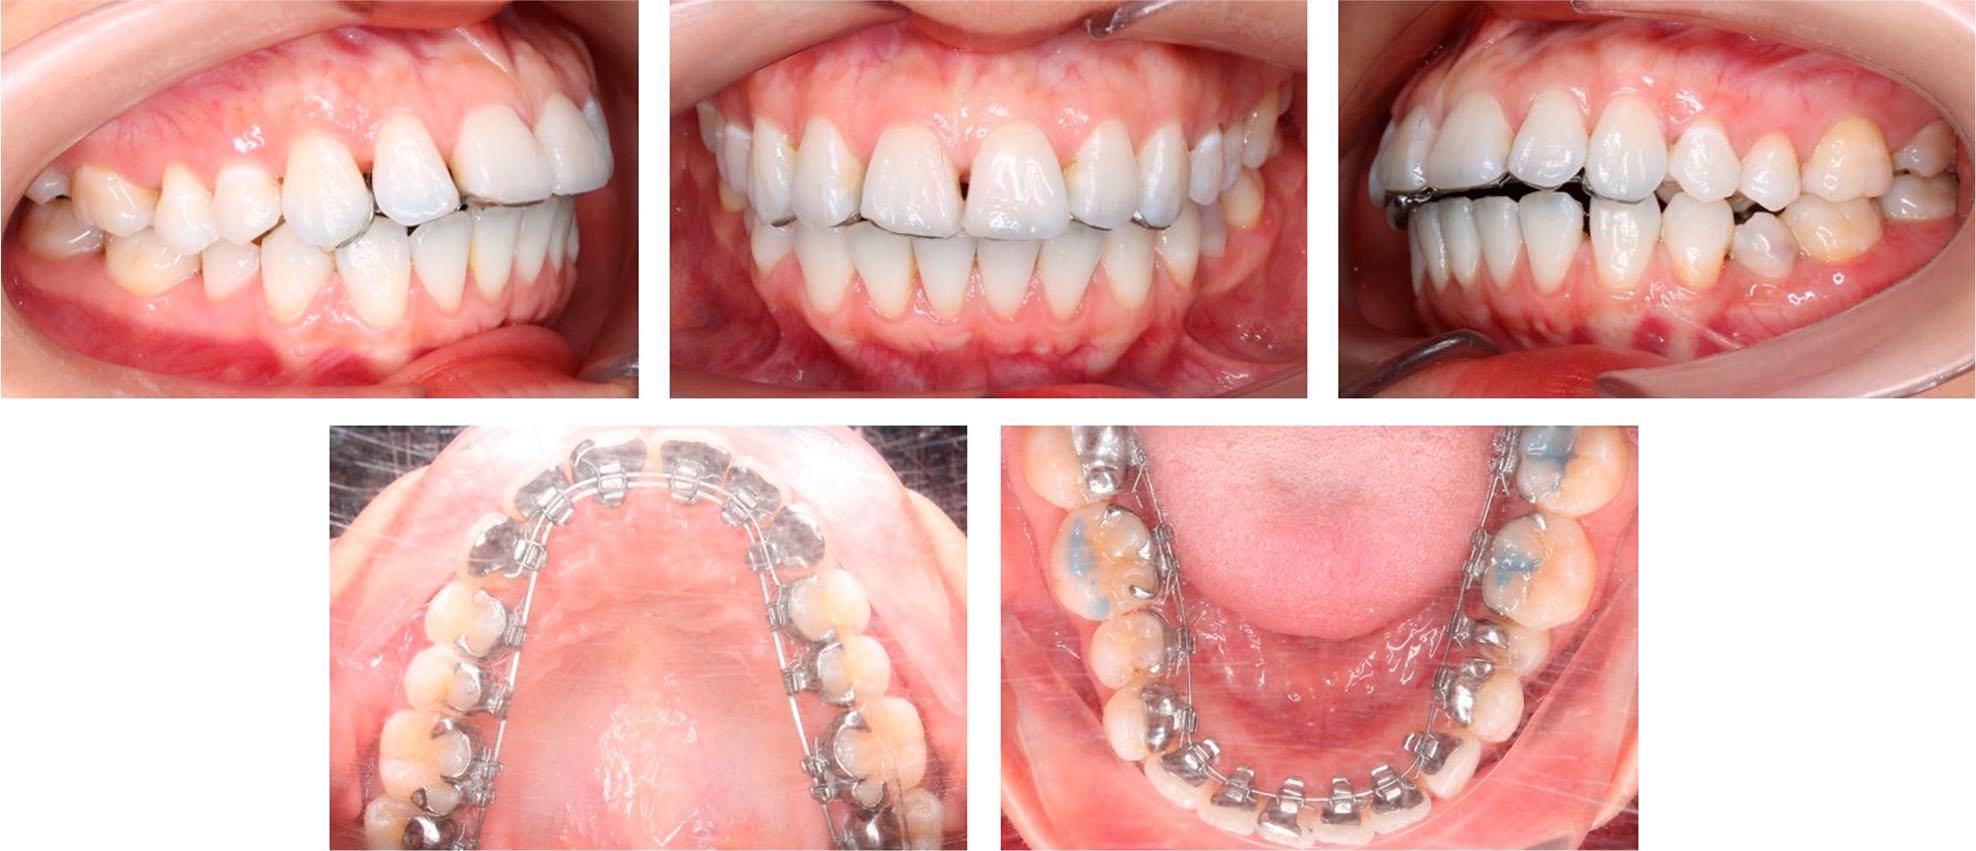

Figure 2.

Figure 3.